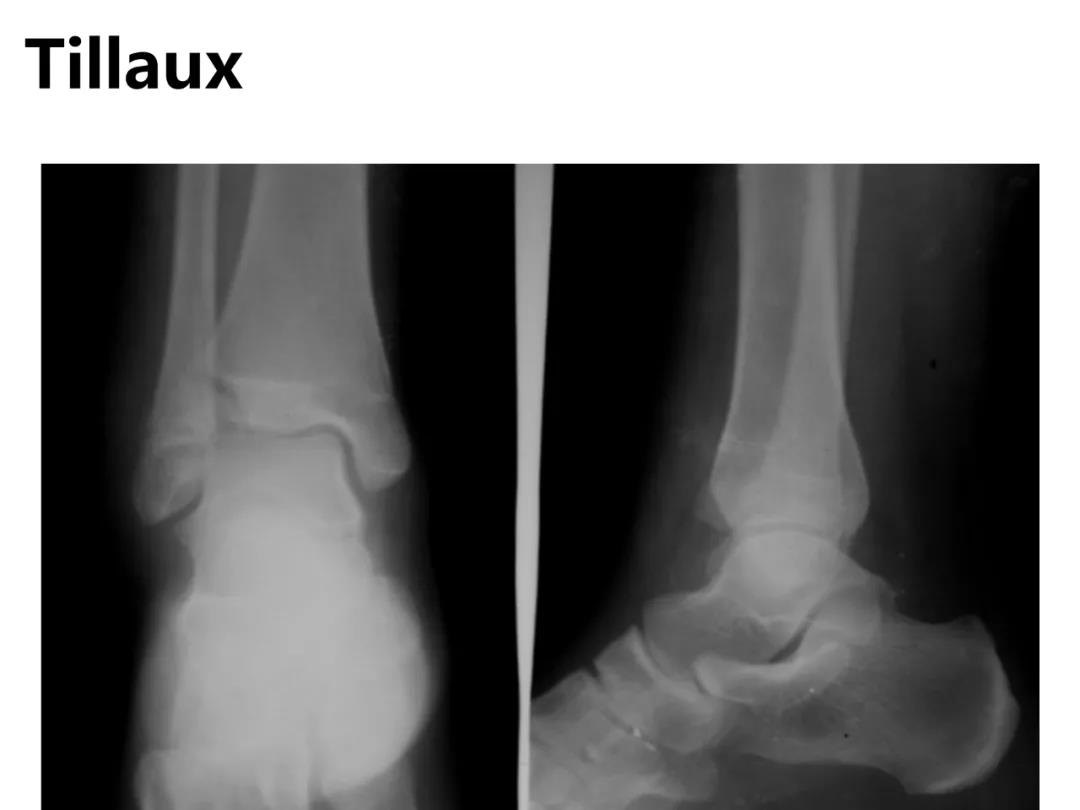

小儿骨科X线片汇总,临床读片宝典!